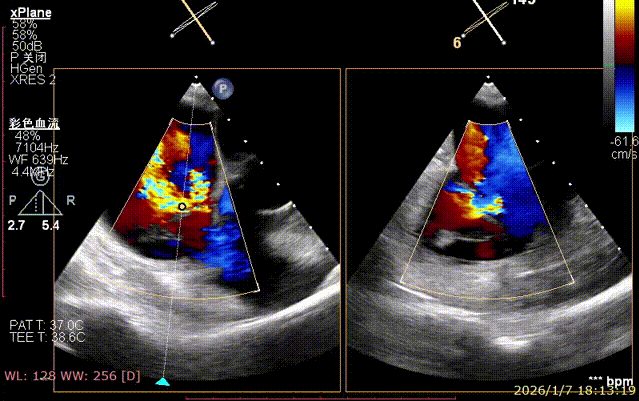

Mitral Valve Repair Stage: Via the transfemoral venous approach, a 4.0 cm atrial septal puncture was performed, and one mitral valve clip was selected. The unique feature of wide-angle deployment effectively resolved the issue of excessive leaflet tension during valve clip closure. Under the precise guidance of ultrasound, one clip was successfully implanted at the site of the widest regurgitation in the A2-P2 segment of the mitral valve. Immediate postoperative TEE assessment showed that mitral regurgitation was reduced to trivial (1+), the mean transvalvular pressure gradient was only 3 mmHg, and pulmonary venous retrograde flow was significantly improved.

Regurgitation Essentially Eliminated at 25° Closure

Trivial Residual Regurgitation Post Deployment

Stable Tissue Bridge